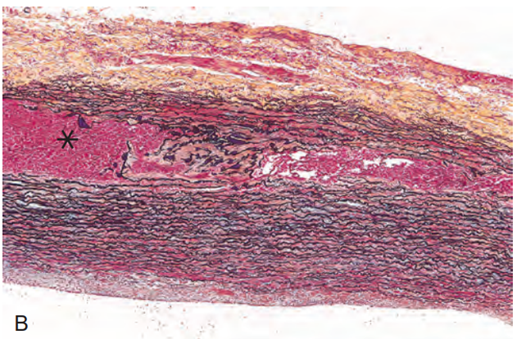

Vad innebär aortadissektion och på vilka sätt kan det ske?

Aortadissektion

Vad ser du på bilden?

Falsk lumen på denna bild